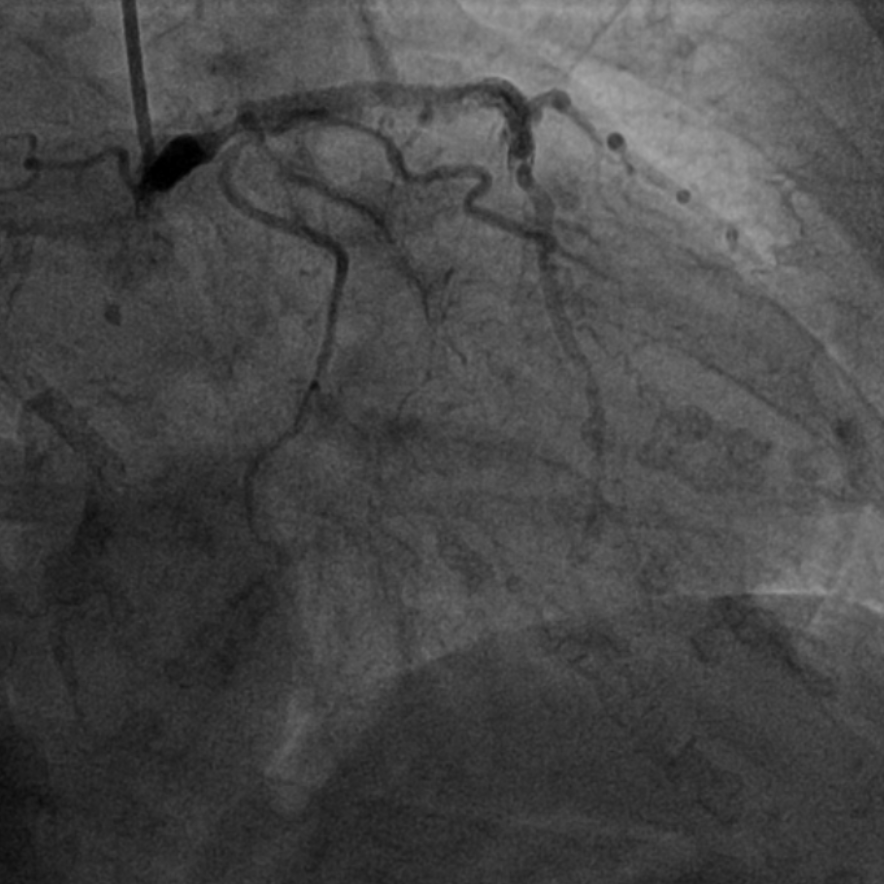

图2 术前造影提示多处再狭窄,冠脉钙化明显

该患者入院后,完善相关检查并再次建议行CABG治疗,但家属仍拒绝,遂考虑再次行PCI手术干预。冠脉造影提示患者冠脉右冠状动脉中段70-95%再狭窄,左主干末端80%狭窄,前降支原支架中远段 80-95%再狭窄,回旋支完全闭塞,急需手术尽快解决冠脉血流灌注问题,否则随时有生命风险,但患者多处支架内/节段内再狭窄,造影提示钙化明显,外院已尝试无法扩张,经手术团队充分讨论后,计划在IABP支持下,先进行右冠状动脉干预,利用IVUS精准评估原支架再狭窄部位情况,采用旋磨或Shockwave冲击波球囊处理无法扩张的病变部位,右冠处理后择期进行左冠状动脉干预。在制定了详尽的手术计划后,手术团队首先对患者的右冠状动脉行IVUS检查,结果提示该患者右冠中段支架局部膨胀不良,局部支架面积6.67mm²,管腔内多处可见钙化小结及270°以上钙化,IVUS钙化积分达3分。由于膨胀不良处原支架后方可见钙化斑块,常规旋磨效果不佳,对于此类钙化病变,IVL处理是最佳方案。手术团队对近端采取棘突球囊及高压球囊进行扩张,采用Guidezilla辅助下输送3.0mmx12mm Shockwave冲击波球囊于右冠钙化处进行冲击波钙化斑块碎裂术,通过IVUS证实支架内的新生钙化病变得到松解,原膨胀不良部位支架面积达到7.76mm²,后经过高压球囊充分预处理,顺利完成右冠支架植入,术后复查右冠原膨胀不良部位支架面积9.17mm²。